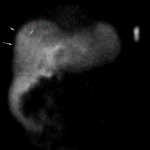

Age: 68

Sex: Male

Indication: Rule out postoperative bile leak, history of TIPS

Radiotracer: Tc99m Mebrofenin

Sample ReportPositive for biliary leak with bile collecting in the right sub-diaphragmatic region and in the right paracolic gutter.